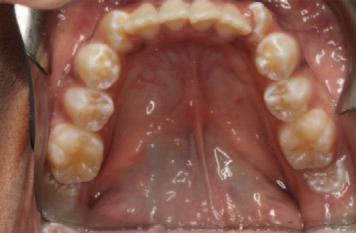

Caries risk assessment in practice

The caries risk status informs the development and implementation of a personalised caries management plan for each patient. Preventive measures, bitewing radiograph intervals and recall planning can be tailored for each patient, in accordance with national and international guidelines.11,13-15 Furthermore, restorative treatment decisions may also be influenced, e.g., interim highviscosity glass ionomer restoration for a high-caries-risk patient with multiple lesions, in contrast to a definitive composite restoration in a patient for whom caries risk can be more readily controlled. Tables 1 and 2 illustrate this tailored approach for different age groups, categorised by caries risk status. These tables represent sample protocols and it is acknowledged that variation will exist depending on local needs, preferred guidance and clinical experience. The personas in Figures 2-4 illustrate the practical application of CRA in general dental practice.

Personae 3 and 4: Daniel and Kayla

Daniel and Kayla are seven-year-old twins. They live with their parents in an estate in a large town. They are both outgoing and busy children. They enjoy school and activities with their friends. Daniel has mild autism. He has a special needs assistant in his classroom who helps him with his reading and language activities.

Daniel and Kayla have had uneventful visits to their family dentist once a year since infancy. Their teeth are brushed twice daily by their father. It is more challenging for Daniel as he does not always cope well with the flavour of the toothpaste. Recently, Daniel has found it more difficult due to sensitivity. Their dentist advised that Daniel has molar incisor hypomineralisation (MIH) and there was enamel breakdown on his newly erupted lower first permanent molars. Kayla’s teeth appeared normal. Bitewing radiographs showed that Kayla’s teeth were intact, but there were uncavitated lesions evident on Daniel’s primary molars.

FIGURE 4: Personae 3 and 4 – Daniel and Kayla.